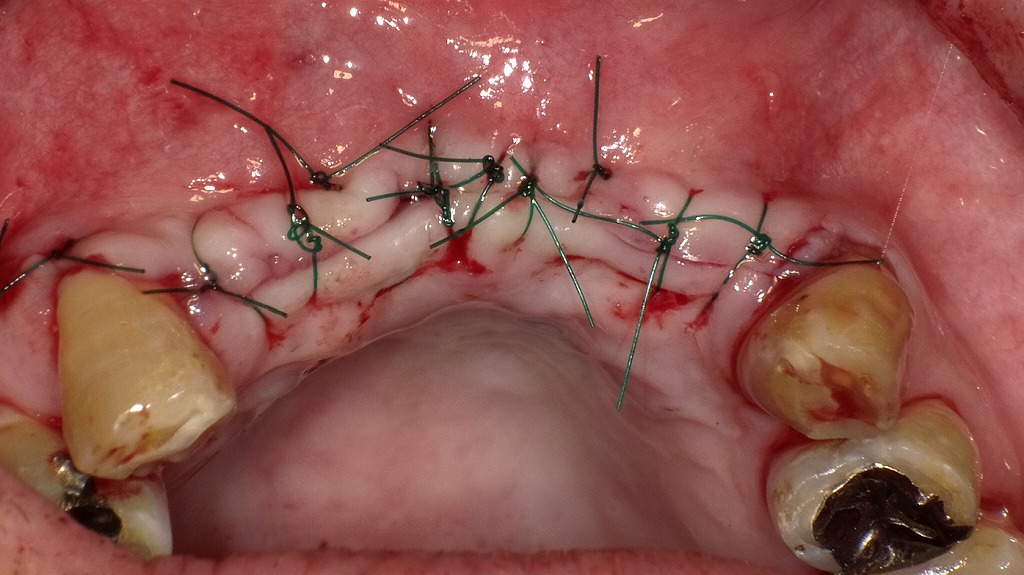

再根管治療後に根尖病巣が治癒

このX線画像は、前回の根尖病巣が治癒した再根管治療後の経過症例を示しています。以下のように説明できます。

🦷 所見の概要

- 対象歯:上顎右側2番(側切歯)・3番(犬歯)

- 画像の特徴:以前認められた根尖部のX線透過像(黒い影)が消失しており、周囲骨の構造が再生していることが確認できます。

- 診断名:根尖性歯周炎の治癒(根尖病巣消失)

🔍 治療の流れ

- メタルコアの除去

- 初回治療時に挿入されていた金属製ポストを慎重に除去。

- これにより、根管内部へのアクセスが確保されました。

- 再根管治療(リトリートメント)

- 旧充填材(ガッタパーチャ)を除去し、感染源となっていた細菌や壊死組織を徹底的に清掃・消毒。

- 根尖まで確実に根管充填を行い、密閉性を改善。

- 根尖病巣の治癒

- 数か月〜1年の経過で、骨の再生が進み、黒い透過像(病巣部)が消失。

- X線上で正常な骨の密度に戻っています。

- 最終補綴(メタルボンドクラウン)

- 治癒後、強度と審美性を両立するメタルボンド冠を装着。

- 噛み合わせ・見た目ともに良好な状態が維持されています。

🩺 まとめ

この症例は、根管治療のやり直しによって感染を除去し、歯を抜かずに治癒へ導いた成功例です。

根尖部の病巣は完全に吸収され、周囲骨が再生していることから、再根管治療の効果が明確に確認できます。